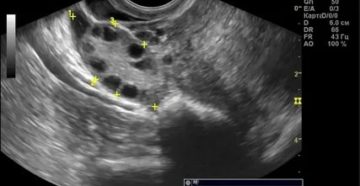

Мультифолликулярные яичники Яичники в женском организме выполняют одну из важнейших ролей в процессе деторождения, а…